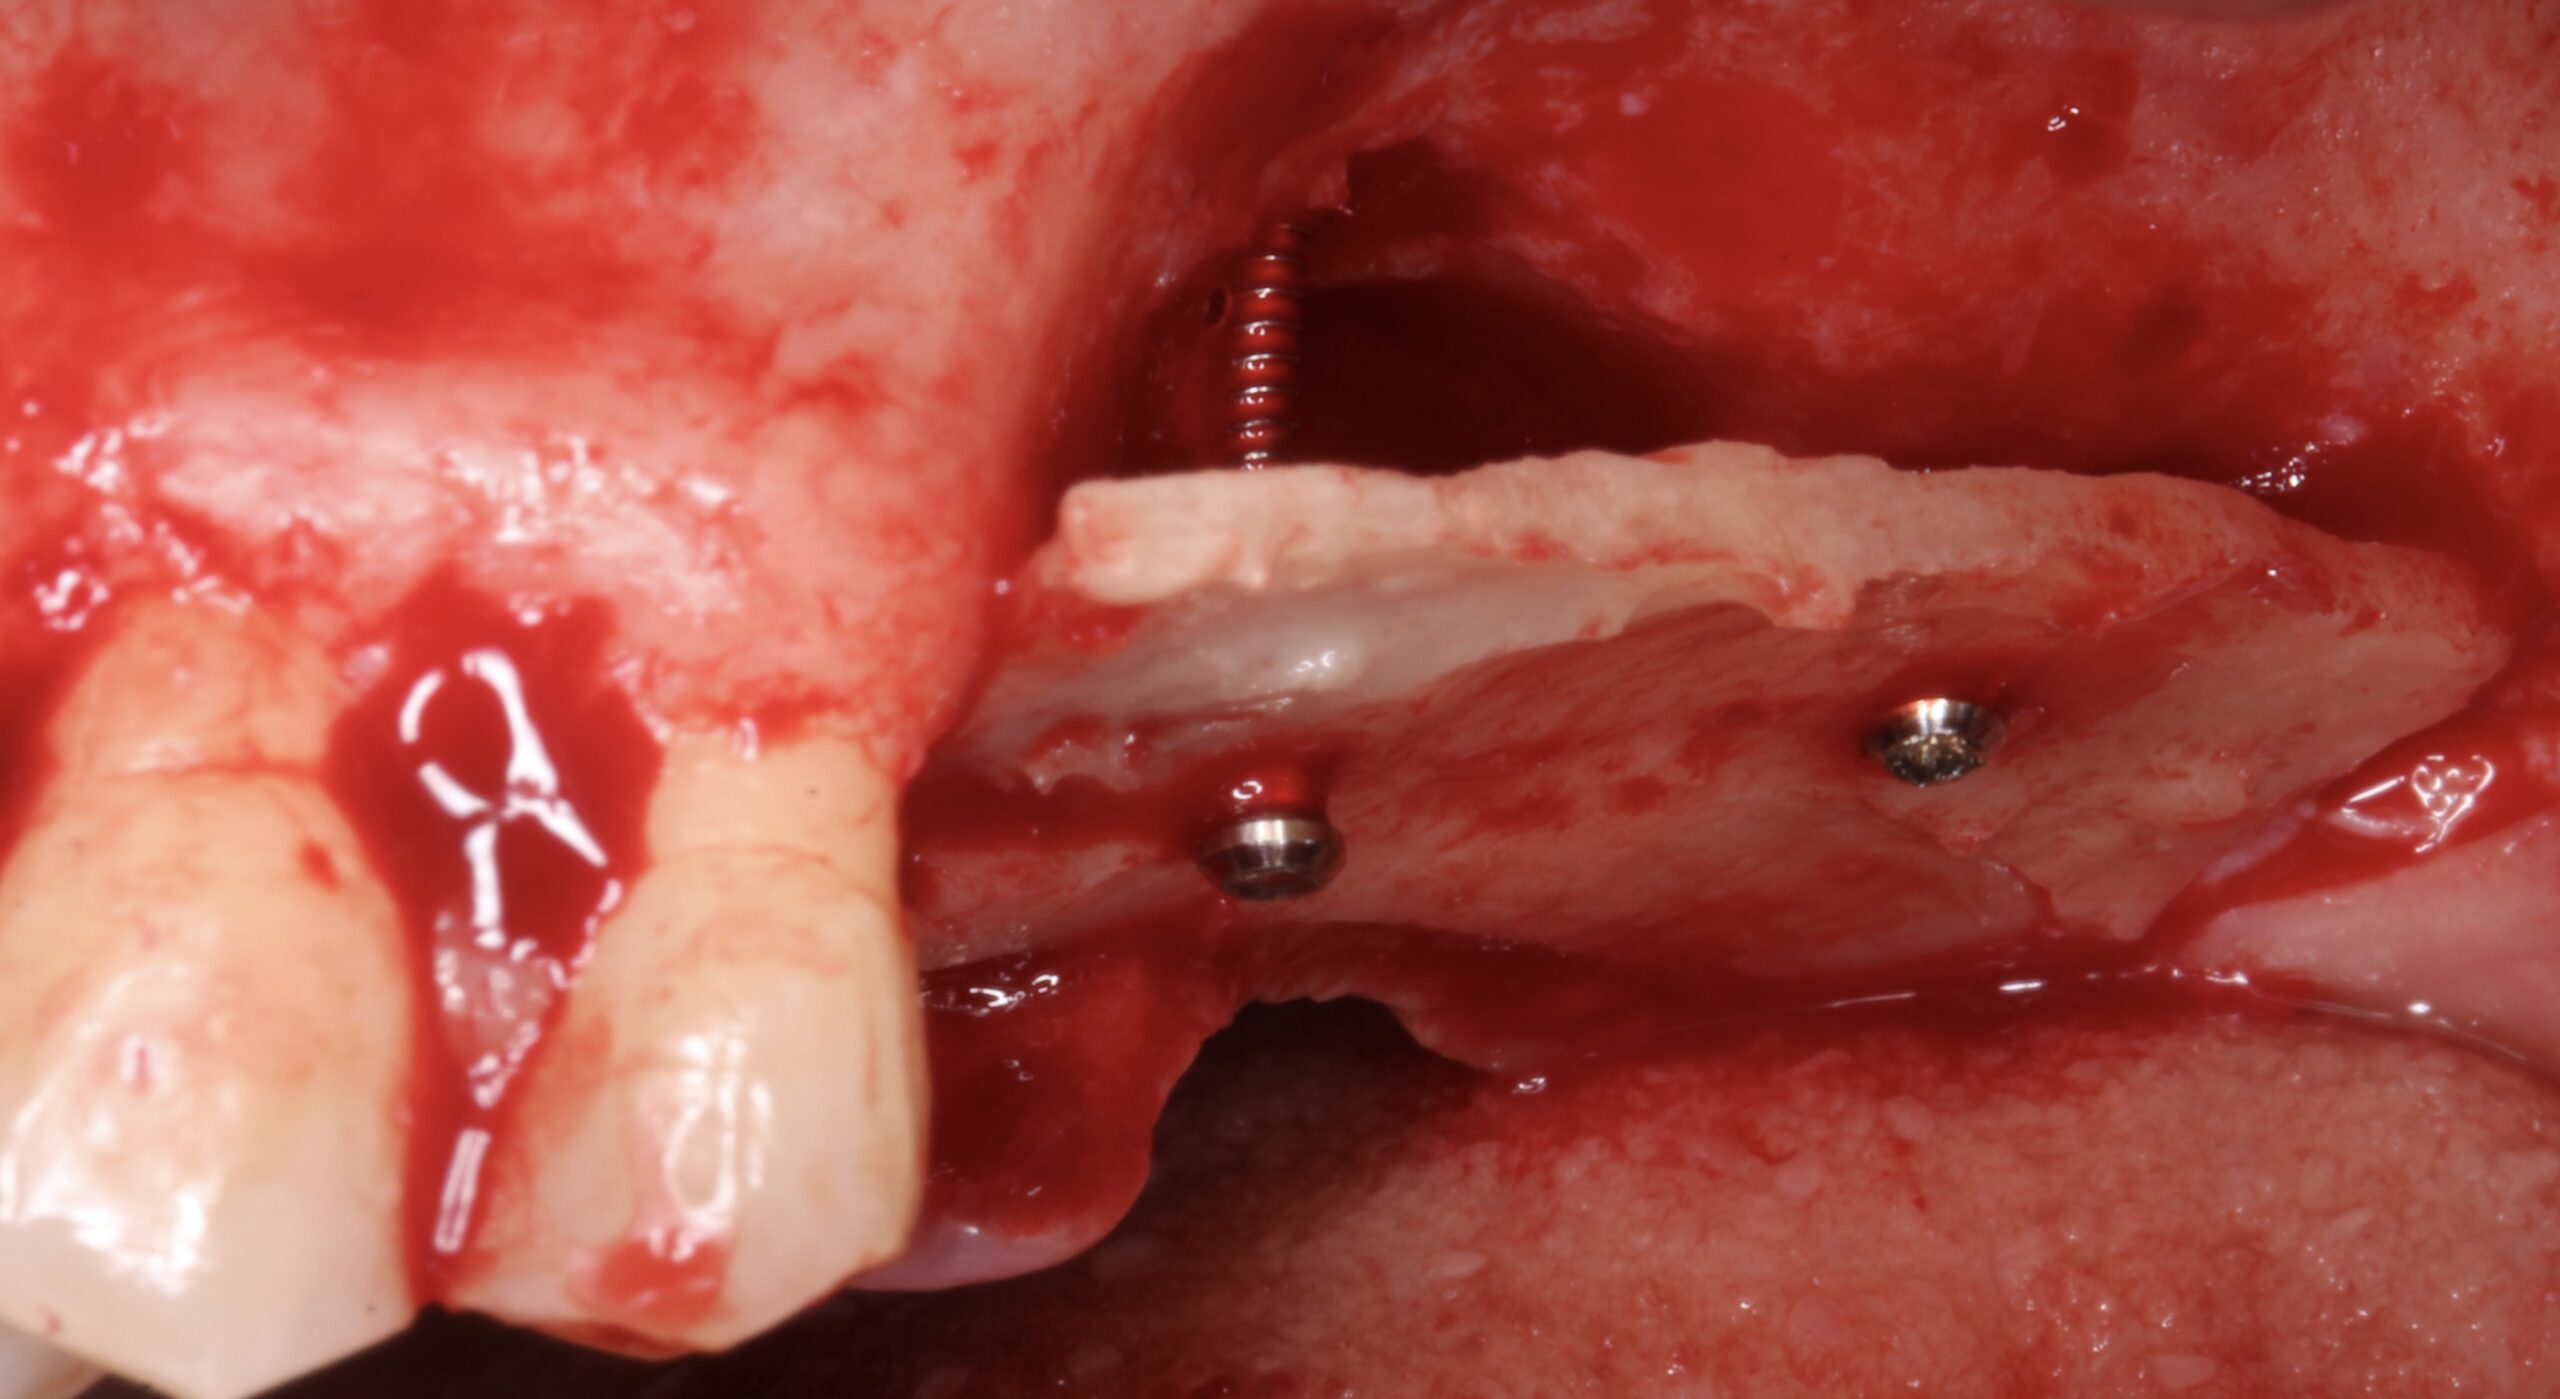

Figure 5.

A split bone block was fixed by screws at the coronal aspect of the alveolar ridge from peak to peak.

Figure 6.

The gap between the block and the alveolar ridge was filled with scraped bone chips.